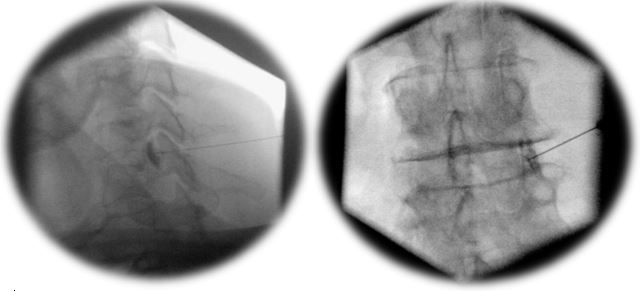

Die Behandlung erfolgt problemorientiert. Dazu gehören Medikamente, Sonographie- und Bildverstärker- gesteuerter Infiltrationen (Spritzen), manuelle Medizin und Physiotherapie.

interventionelle Schmerztherapie (Infiltration mittels Bildverstärker/Ultraschall)

Die interventionelle Schmerztherapie mit Infiltration unter Verwendung von Bildgebungstechniken wie Durchleuchtung (BV) und Sonographie ist ein spezialisiertes Verfahren zur gezielten Behandlung von Schmerzen.

- Diagnose und Lokalisation von Schmerzursachen mithilfe von Bildgebungstechniken wie Durchleuchtung und Sonographie

- Durchführung von gezielten Infiltrationen zur gezielten Schmerzbehandlung an betroffenen Stellen wie Gelenken, Nerven oder Weichteilgewebe

- Anwendung von lokalen Betäubungsmitteln, Steroiden oder anderen Medikamenten zur Schmerzlinderung und Entzündungshemmung

- Überwachung und Kontrolle der Infiltrationstechniken unter Bildgebung, um eine präzise und sichere Behandlung zu gewährleisten

Die interventionelle Schmerztherapie mit Infiltration und Bildgebungstechniken bietet eine effektive und schonende Methode zur gezielten Behandlung von Schmerzen, insbesondere bei chronischen Schmerzsyndromen.